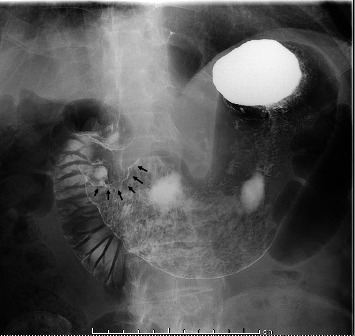

背景:人表皮生长因子受体2 (HER2)阳性胃癌约占胃癌病例的15%。曲妥珠单抗(Trz)是一种靶向HER2的单克隆抗体,已被证明与化疗联合可提高总生存率。然而,虽然trz诱导的心脏毒性(TIC)是乳腺癌化疗中公认的不良反应,但关于其在胃癌治疗中的发生的报道仍然有限。病例介绍:一名80岁日本男性her2阳性晚期胃癌(ciii期)患者在术后使用Trz + SOX方案(Trz、奥沙利铂和TS-1)化疗时出现室性心律失常和心力衰竭。患者最初因贫血和幽门狭窄行远端胃切除术并D1+淋巴结切除术。转移到#8a淋巴结(肝总动脉前上淋巴结)和通过淋巴结侵入胰腺的患者采用两个周期的Trz + SOX方案治疗,导致部分缓解。然而,在第11个周期后,他出现室性心动过速和心力衰竭。心脏影像学和实验室检查未发现冠状动脉病变或结构异常,提示TIC是根本原因。药物抗心律失常治疗导致症状缓解,无心律失常或心力衰竭复发。讨论:本病例强调了以非蒽环类药物为基础的Trz治疗胃癌的潜在心脏毒性。病理生理学上,HER2信号抑制可能会损害心肌细胞的应激反应和修复机制。患者的高龄、高血压和贫血史以及长期接受化疗可能是心脏易感性增加的原因。仔细监测心功能对于接受trz为基础的胃癌治疗的老年和合并症患者至关重要,以减轻心脏毒性的风险。结论:以trz为基础的化疗治疗her2阳性胃癌,即使不使用蒽环类药物,也可能造成心脏毒性的风险,特别是在老年人或合并症患者中。需要进一步的研究来阐明潜在的机制,优化这一人群的监测和预防策略。

Background: Human epidermal growth factor receptor 2 (HER2)-positive gastric cancer accounts for approximately 15% of gastric cancer cases. Trastuzumab (Trz), a monoclonal antibody targeting HER2, has been shown to improve overall survival when combined with chemotherapy. However, while Trz-induced cardiotoxicity (TIC) is a well-recognized adverse effect in breast cancer chemotherapy, reports on its occurrence in gastric cancer treatment remain limited. Case Presentation: An 80-year-old Japanese male with HER2-positive advanced gastric cancer (cStage III) developed ventricular arrhythmia and heart failure during postoperative chemotherapy with the Trz + SOX regimen (Trz, oxaliplatin, and TS-1). The patient initially underwent distal gastrectomy with D1+ lymphadenectomy for anemia and pyloric stenosis. Metastasis to the #8a lymph node (anterior superior lymph node of the common hepatic artery) and pancreatic invasion via lymph nodes were treated with two cycles of the Trz + SOX regimen, leading to a partial response. However, after the 11th cycle, he developed ventricular tachycardia and heart failure. Cardiac imaging and laboratory findings revealed no coronary artery disease or structural abnormalities, suggesting TIC as the underlying cause. Antiarrhythmic therapy with pharmacological agents led to symptom resolution, and no recurrence of arrhythmia or heart failure was observed. Discussion: This case highlights the potential cardiotoxicity associated with nonanthracycline-based Trz regimens for gastric cancer. Pathophysiologically, HER2 signaling inhibition in cardiomyocytes may impair stress responses and repair mechanisms. The patient's advanced age, history of hypertension and anemia, and cumulative exposure to chemotherapy may have contributed to increased cardiac vulnerability. Careful monitoring of cardiac function is essential in elderly and comorbid patients undergoing Trz-based therapy for gastric cancer to mitigate the risk of cardiotoxicity. Conclusion: Trz-based chemotherapy for HER2-positive gastric cancer, even without anthracyclines, may pose a risk of cardiotoxicity, particularly in elderly or comorbid patients. Further research is warranted to elucidate underlying mechanisms and optimize monitoring and prevention strategies in this population.